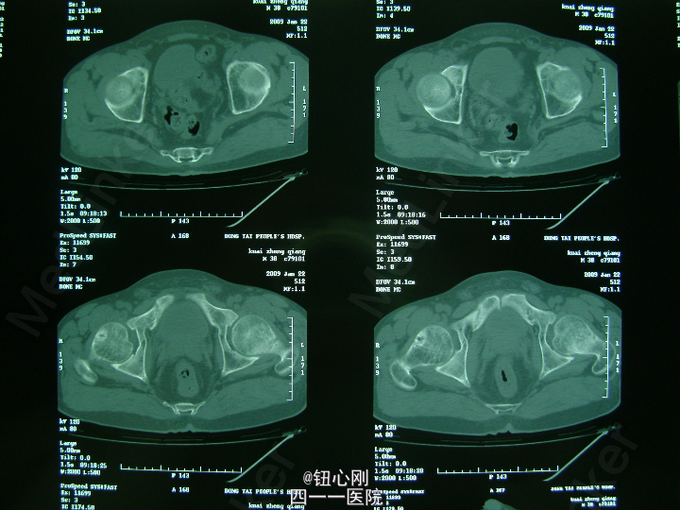

男,38岁,主诉全身多处骨关节疼痛5年。5年内身高降低5厘米,活动后全身关节疼痛加重,休息后减轻。疼痛以腰椎,全身大关节为主。既往体健,否认有肾功能不全及胃肠道病史,肝胆胰腺病史,无激素及其他特殊药物使用史。无毒物接触史。饮食正常,家族中无类似病史

查体间:略有驼背畸形,全身大关节及脊柱活动性降低,大关节处有明显叩压痛。 辅助检查:三大常规,肝肾功正常,血沉正常,各肿瘤指标正常,钙正常,血磷减低(0.44mmol/L),骨特异性碱性磷酸酶升高(99.95ng/L),PTH、CT正常,尿本周蛋白(-),血清蛋白电泳正常,无M蛋白,血皮质醇正常。 胸片,心电图,肝胆胰脾双肾B超正常。

病史特点:1、壮年男性,以全身多处骨痛为主,伴身高降低为主诉;2、体检可见:驼背畸形,脊柱及四肢大关节处活动降低,有叩压痛;3、辅助检查提示:血磷减低,血钙正常,影像学显示:全身骨骼骨质疏松改变,未见其它骨破坏。 鉴别诊断:排除骨髓瘤,转移性肿瘤,甲状旁腺亢进,肾性骨病,原发性及药物性骨质疏松 诊断:成人低磷性骨软化症 治疗:予以钙片、骨化三醇,中性磷酸盐口服